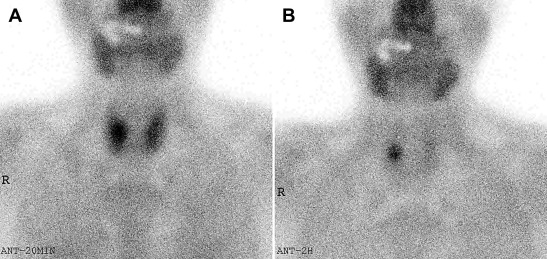

MIBI scintigraphy. (A) MIBI uptake in both thyroid areas 20 minutes after MIBI ...

Figure 3.

MIBI scintigraphy. (A) MIBI uptake in both thyroid areas 20 minutes after MIBI injection and (B) MIBI uptake in the right inferior parathyroid 2 hours after MIBI injection. Uptake lesion was identified intraoperatively as a migrated right superior parathyroid. MIBI = 99mTc-sestamibi.

MIBI scanning is a useful modality for localization of abnormal parathyroid lesions in hyperparathyroidism.11 However, the role of a MIBI scan in diagnosing parathyroid carcinoma in secondary or tertiary hyperparathyroidism is, as yet, not clear.12 The MIBI scan can be used as an indicator of proliferative parathyroid gland activity.13 Parathyroid carcinoma can be assumed to have higher proliferative activity than parathyroid hyperplasia. Therefore, when a lesion of parathyroid carcinoma coexists with other lesions of parathyroid hyperplasia, an increased uptake in the MIBI scan is suggestive of parathyroid carcinoma.

In our case, a 2-hour delayed MIBI scan showed an increased uptake in the right inferior gland. However, parathyroid carcinoma was later found in the right superior parathyroid gland. This discordance can be due to the fact that the superior parathyroids, when tumorous, may migrate posteriorly and inferiorly, and often appear as higher uptake in the inferior location on MIBI scan.14 In fact, we identified migrated right superior parathyroid tumors in posterior and inferior positions, intraoperatively. Single-photon emission computed tomography MIBI scan is helpful in differentiating between superior and inferior parathyroid lesions.15 ;  16